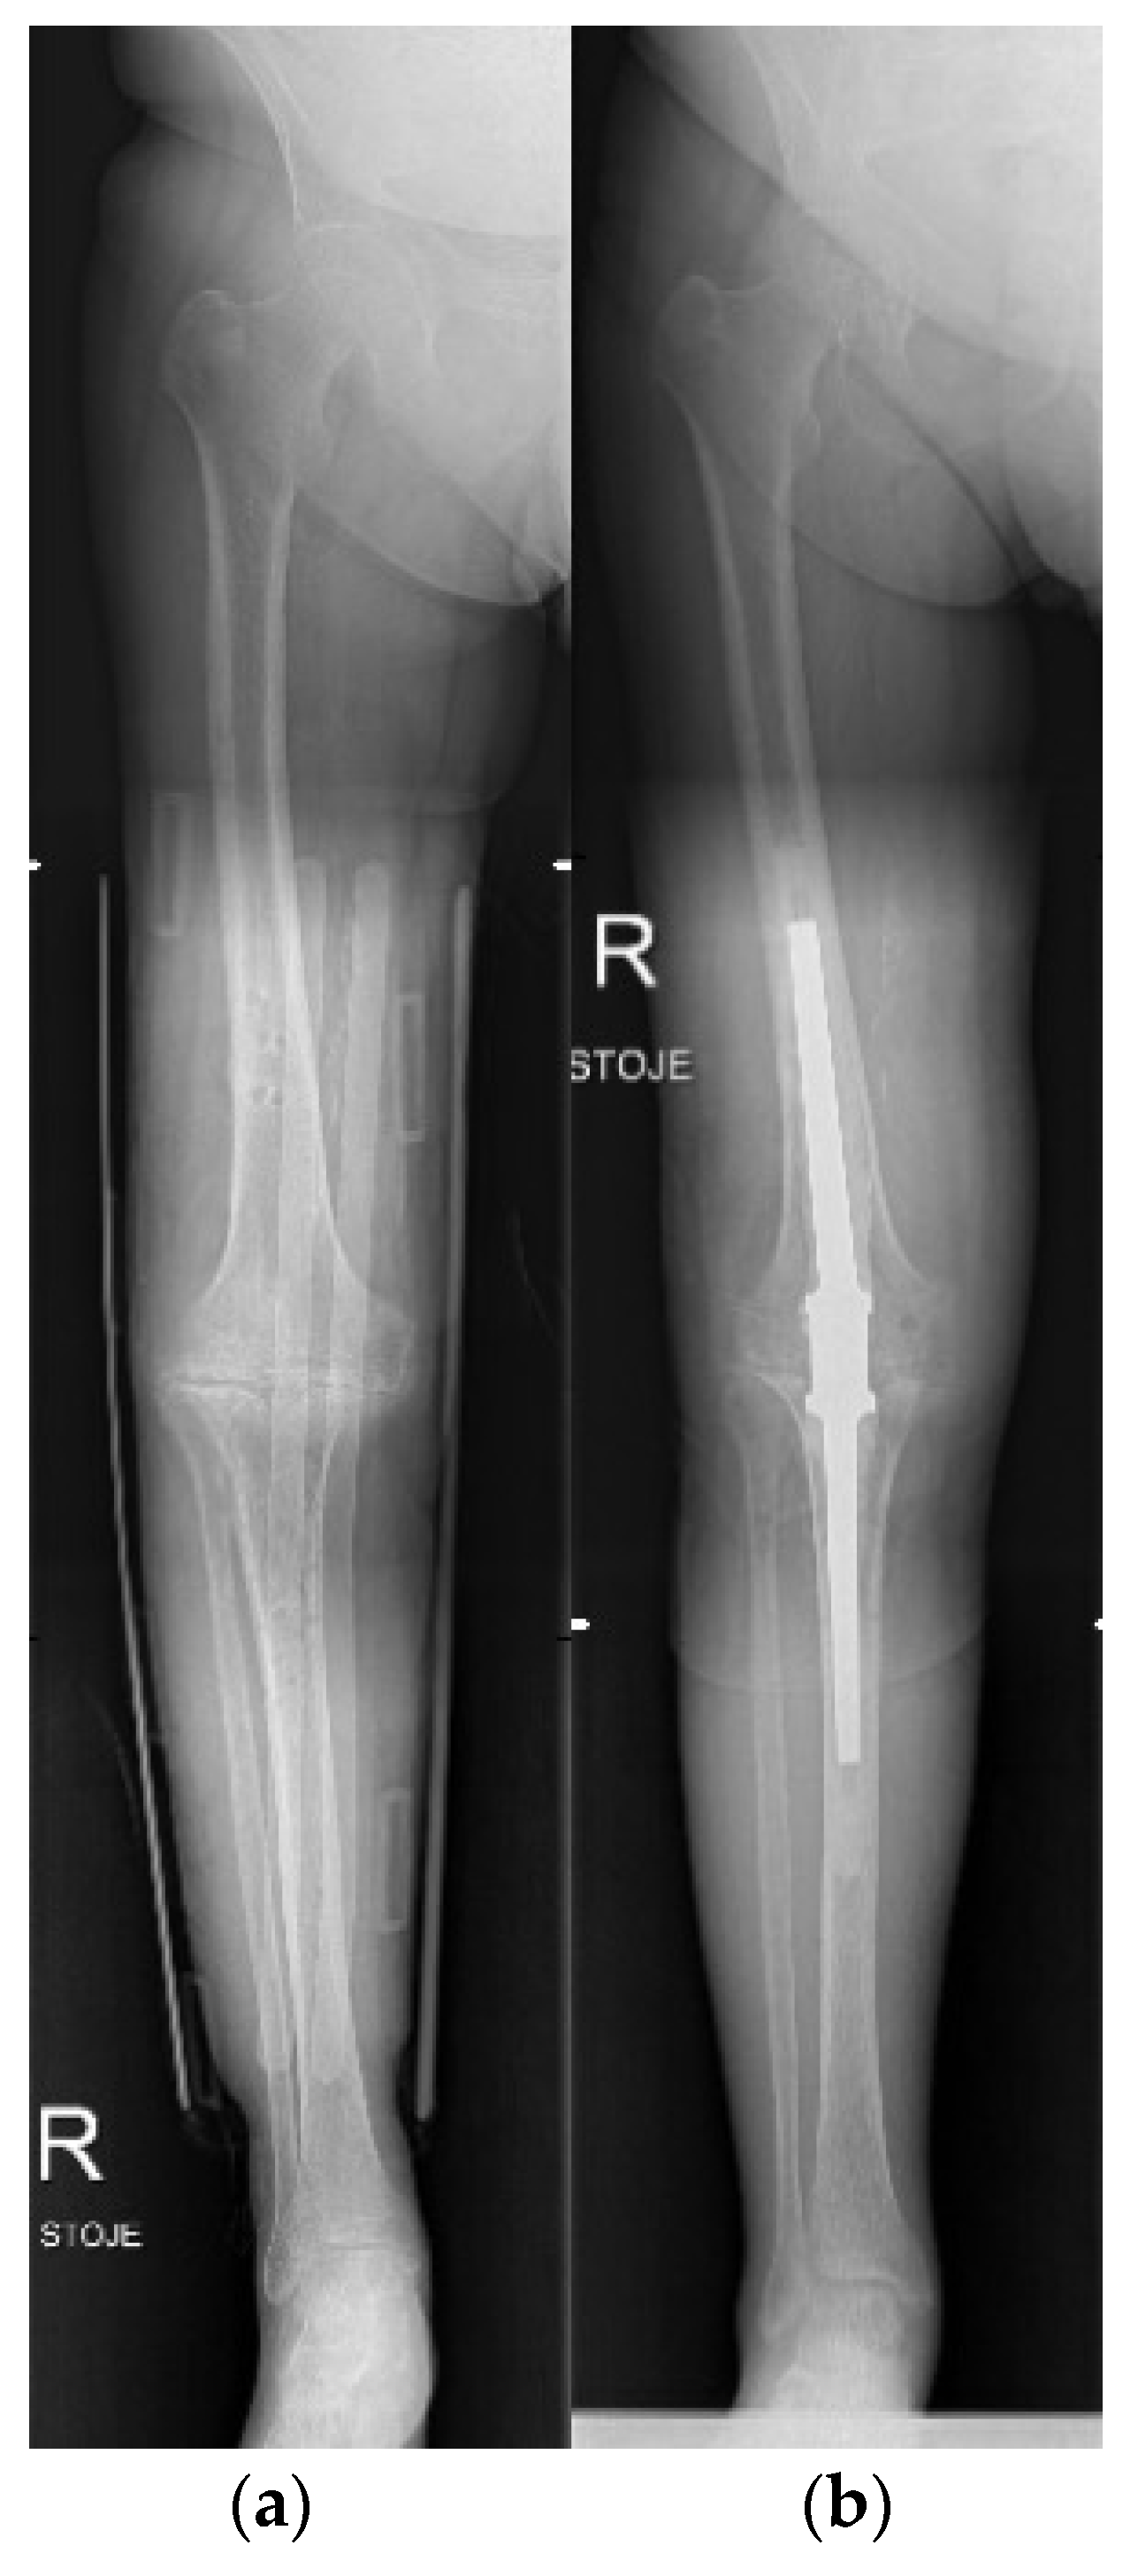

4.6. Knee

- Wood, J.H.; Conway, J.D. Advanced Concepts in Knee Arthrodesis. World J. Orthop. 2015, 6, 202–210. [Google Scholar] [CrossRef]

- Acquitter, Y.; Hulet, C.; Souquet, D.; Pierre, A.; Locker, B.; Vielpeau, C. Arthroscopic knee arthrodesis: 4 cases. Rev. Chir. Orthop. Reparatrice Appar. Mot. 2004, 90, 65–70. [Google Scholar] [CrossRef]

- Waszczykowski, M.; Niedzielski, K.; Radek, M.; Fabis, J. Arthroscopic-Assisted Arthrodesis of the Knee Joint With the Ilizarov Technique: A Case Report and Literature Review. Medicine 2016, 95, e2540. [Google Scholar] [CrossRef] [PubMed]